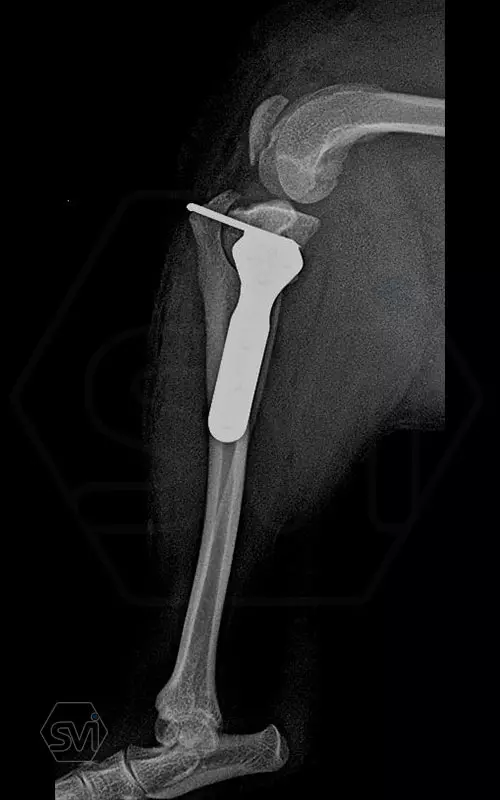

Mini TPLO-M plate:

non-locking, symmetrical, with 2.2 mm terrace (degree of shift), for standard 2.0 mm AO cortical screws (1.5 and 2.4 mm screws can also be inserted), material steel. Optimized for R12 blades.

Between October 2020 and December 2021, we performed 19 TPLO-M surgeries at the Animal Hospital in Nyíregyháza,: 16 times used the mini (2.0 R12) and 3 times the small (2,4 R15) TPLO-M plate.

The experience is very encouraging, we find the system and plates suitable for the simultaneous treatment of MPL and RACL. ( in case of 4/4 pat. lux. also). We will back soon with details.